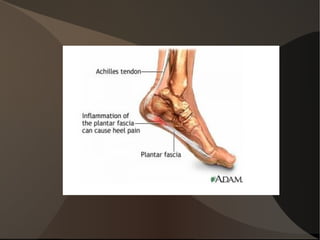

Le muscle Commence et se termine par un tendon

Est fixé à chaque extrémité sur un os par l'intermédiaire du tendon